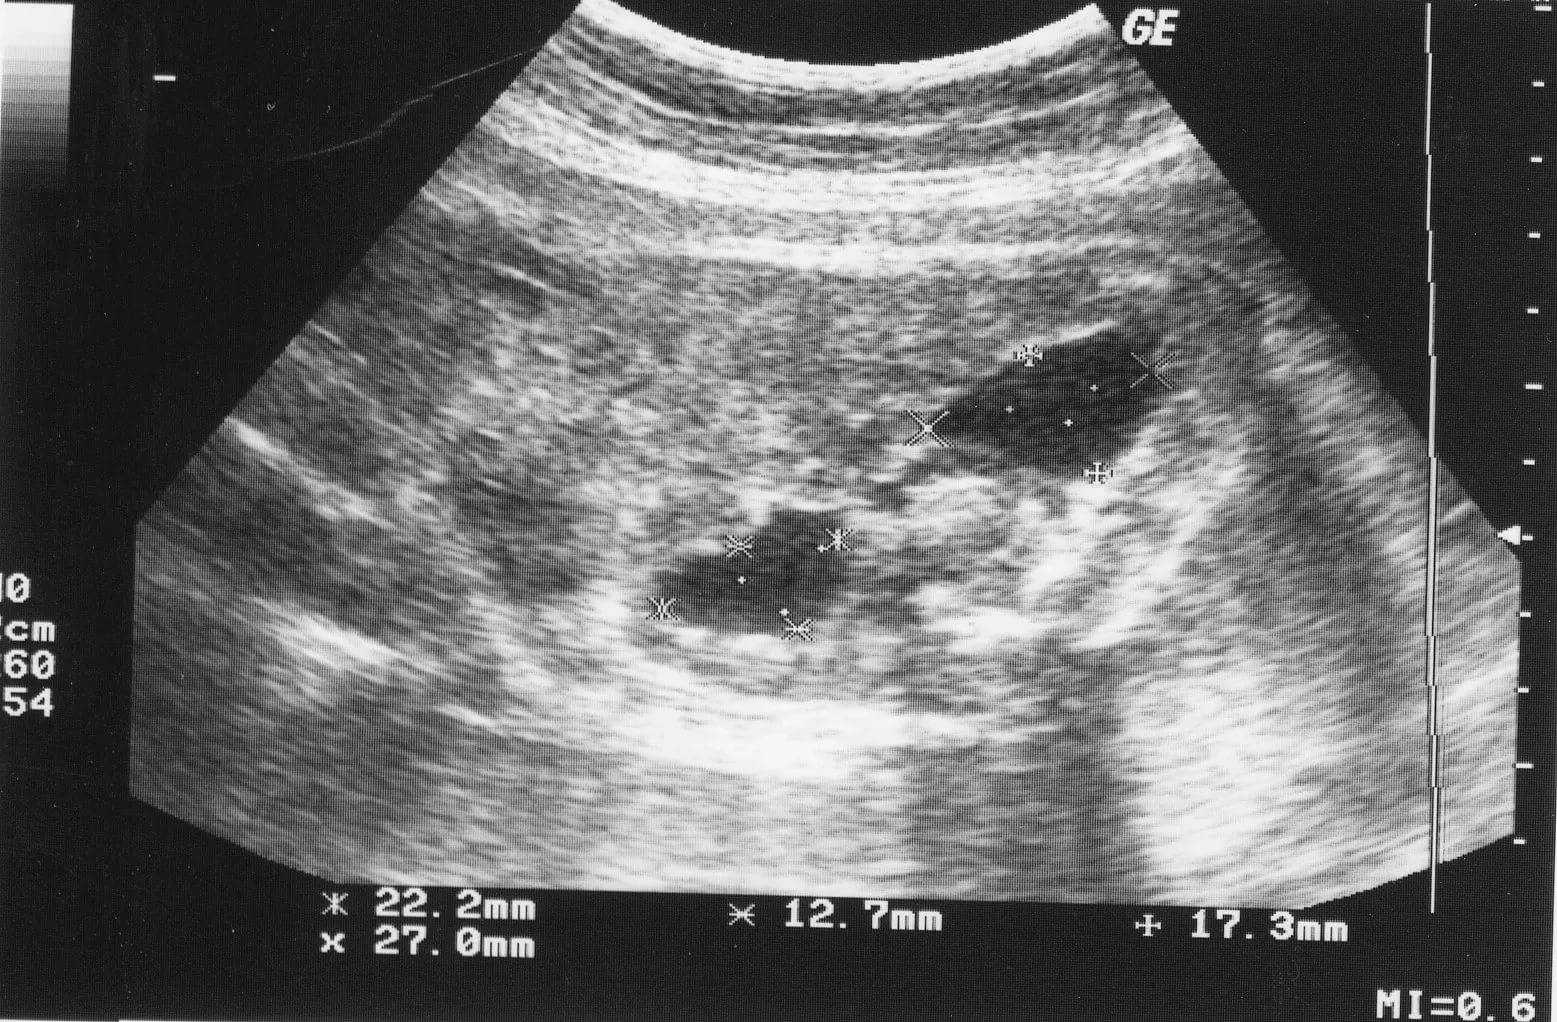

Методы исследования

Основными методами диагностики гидронефроза у детей являются: ультразвуковое исследование, экскреторная урография, нефросцинтиграфия (динамическая, статическая), цистография.Ультразвуковое исследование почек прекрасный метод как для скринингового, так и диагностического обследования пациентов. Данным методом можно выявить расширение чашечно-лоханочной системы почки у детей любого возраста. Главным преимуществом метода является его безопасность. У младенцев первых месяцев жизни необходимо проводить дифференциальный диагноз гидронефроза с пиелоэктазией или функциональным расширением ЧЛС, которое исчезает самостоятельно в течении 3-6 мес.С целью дифференциальной диагностики функциональных нарушений и механической обструкции большое значение имеет ультрасонография с лазиксом при достаточной водной нагрузке.Признаками органической обструкции считают:

1. Расширение чашечно-лоханочной системы более 30 % от исходного размера в течение более 60 мин.2. Появление болевого синдрома, тошноты и рвоты.3. Уменьшение скорости почечного кровотока и повышение на 15% индекса сопротивления на фоне лазиксной нагрузки.4. Признаки гипертрофии контрлатеральной почки.